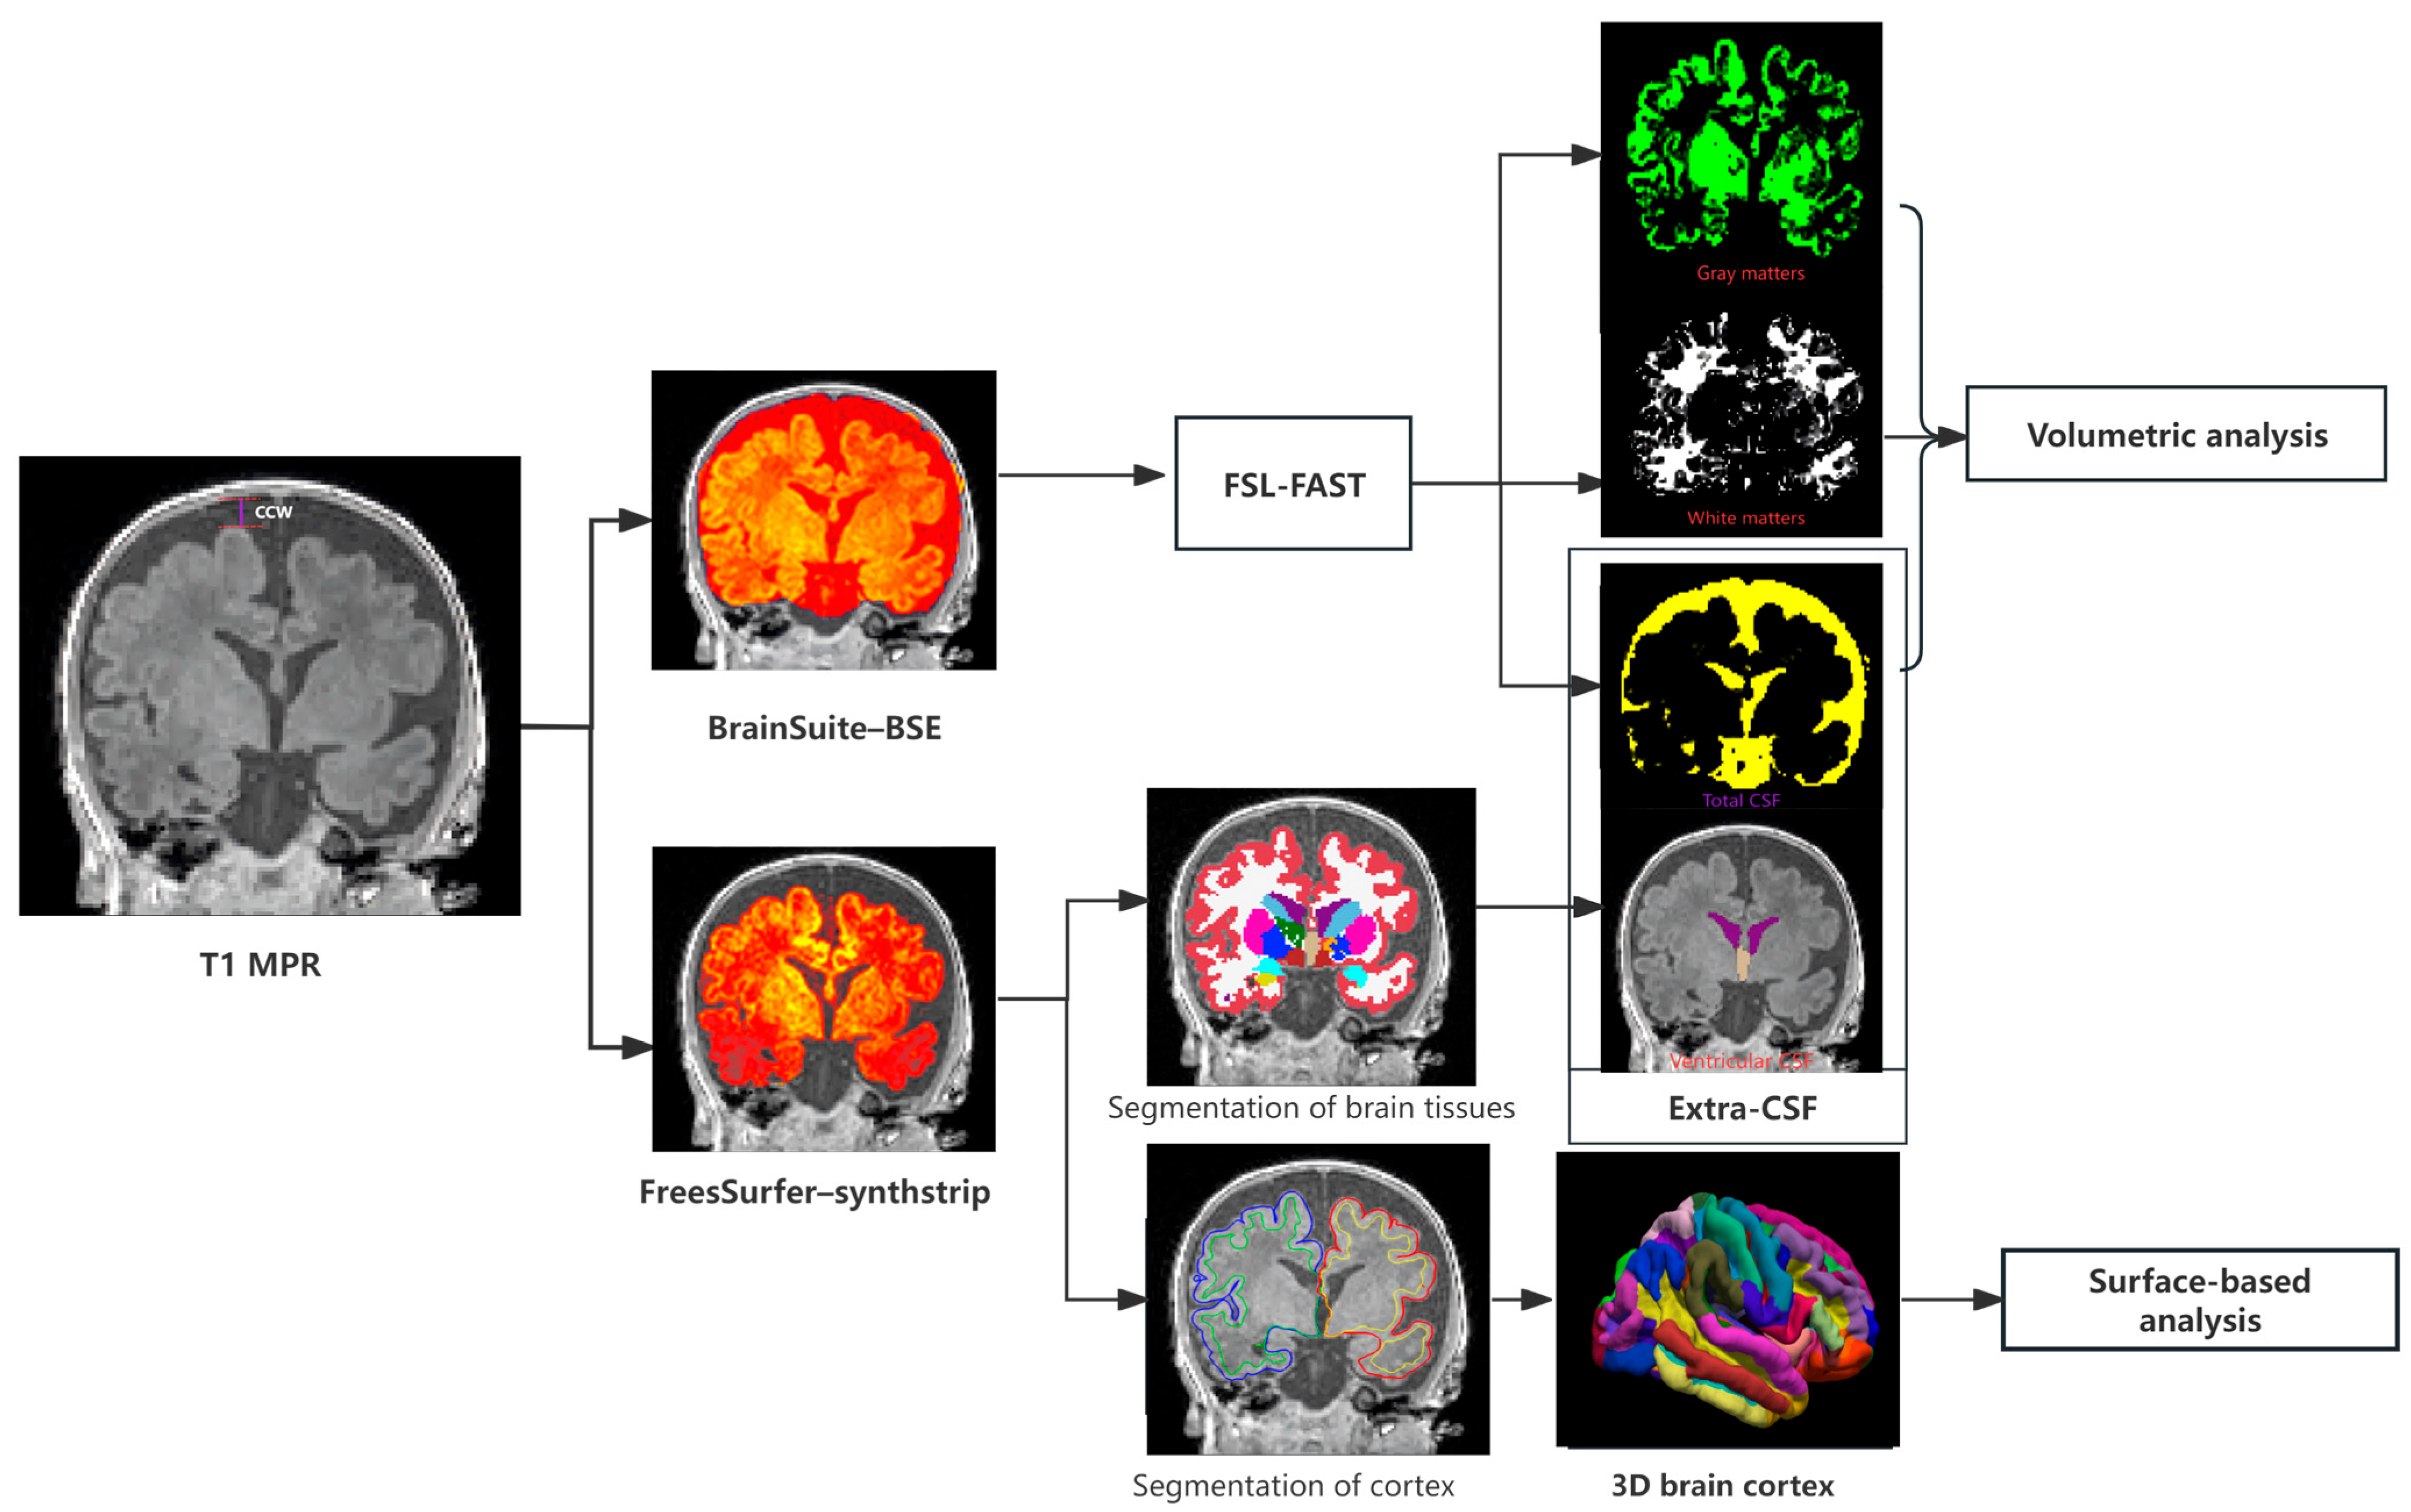

2.4. MR Image Analysis

2.4.2. Brain Tissue Segmentation

2.4.3. Brain Surface Segmentation